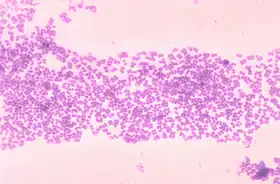

Micrococcus

Micrococcus é um gênero de bactérias do filo Actinobacteria. Normalmente, não são patogênicos, e podem ser essenciais para manter o equilíbrio da flora bacteriana na pele.[1]